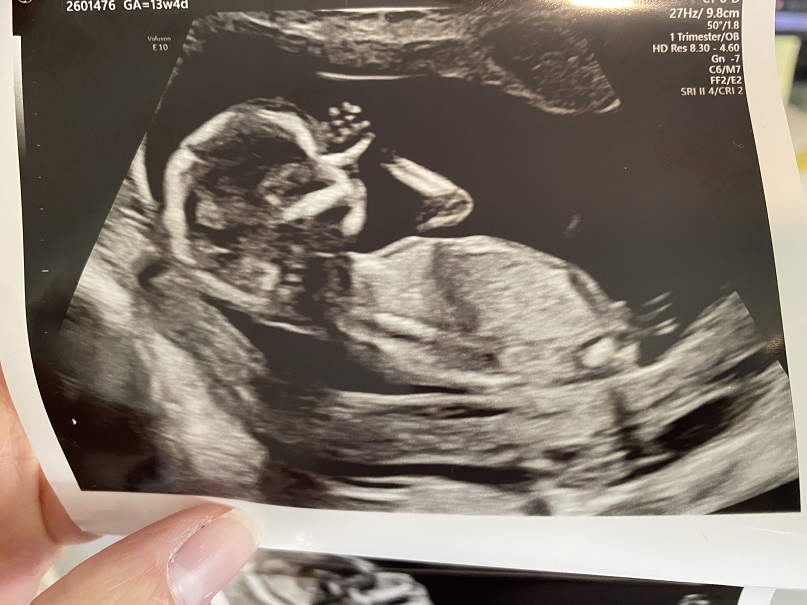

Can anyone point up where the nub is in these pics? 13w 4d NT scan

I posted these pics in a few other forums and got mostly boy leans but some girl ones as well. When I asked if they were basing their guess off of the skull shape or if they can point out the nub to me, nobody replies! Except one lady said her intuition was that it was a girl. Which doesn't give me much hope lol. Ramzi and skull theory seem to point to boy. And even though I didn't get a pic of the potty shot, it looked like a triangle down there so I'm thinking this is a boy. Which will make our 4th boy and last child so I'm feeling a bit gutted and wishing I would have pushed a little harder to convince my husband to go high-tech. I just took my NIPT so we'll find out soon enough. Any guesses are appreciated either way! Let me know if you see a nub!

Attachment 42961Attachment 42962